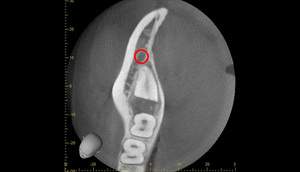

CT画像②

麻布十番歯科での右下の親知らずが真横に生えている症例のCT画像②

CTの1部分の画像です。下歯槽神経と親知らずはほんの少し接触しているような状態でした。リスクなど説明し、2回法で抜いていくことにしました。

2回法とは、その名の通り、2回かけて親知らずを抜いていく方法になります。

1回目は歯の頭の部分だけを切るだけになります。2回目は数ヶ月経ってから行いますが、1回目で頭の部分を取ったスペースに歯が伸びてきますので、下歯槽神経と離れたかを確認してから、根の部分を抜いていく、そういった方法になります。

3ヶ月のCT画像①

麻布十番歯科での1回目の親知らず抜歯から3ヶ月後のCT画像①

3ヶ月のCT画像②

麻布十番歯科での1回目の親知らず抜歯から3ヶ月後のCT画像②

1回目から3ヶ月待ちました。下歯槽神経の位置が根の先から離れているのが確認できます。

これで下歯槽神経を損傷させることなく、親知らずの抜歯を行うことができます。